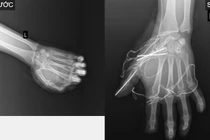

Các bác sĩ tại khoa Phẫu thuật Chấn thương Chỉnh hình và Y học thể thao - Bệnh viện E đã tiếp nhận và điều trị cho một trường hợp chấn thương bàn tay nghiêm trọng do pháo nổ.

Tai nạn chỉ trong tích tắc phá hủy gân, xương, cơ khớp